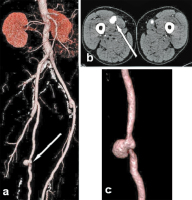

Abbildung 3a-c: Kontrastmittelverstärkte CT-Angiographie. (a): Übersicht nach mehrfacher gefäßchirurgischer Rekonstruktion aorto-bipro-fundal und beidseits femoro-popliteal („volume rendering technique“, VRT), anastomosenferne, gedeckte Bypass-Ruptur mit Pseudoaneurysma rechts (Pfeil); (b): kontrastmittelverstärkte CT-Angiographie (Transversal-Schnitt) des pulsierenden Hämatoms rechts (Pfeil); (c): Aneurysma spurium nach semizirkulärer gedeckter Bypass-Ruptur rechts (VRT).